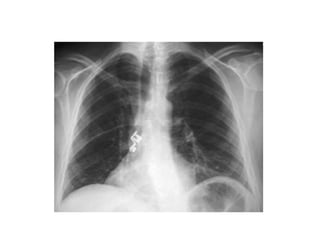

Patrón alveolar difuso EDEMA

PULMONAR

PULMONAR(Distress)